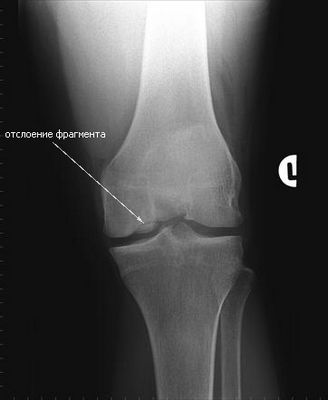

Диагноз рассекающего osteochondritisЧеловек, испытывающий симптомы OCD в суставе, должен обратиться за медицинским советом как можно скорее. Ранее условие диагностируется и лечится, более эффективное лечение будет и ниже риск любых осложнений.Доктор выполняет медицинский осмотр и задает вопросы пациента о его/ее истории болезни, возможно семейная история и образ жизни, включая спортивные действия.

Доктор может приказать, чтобы некоторые анализы отображения, такие как Рентген, Коннектикут или просмотр ЯМР узнали, существует ли какой-либо некроз (смерть ткани) или свободные фрагменты. Рентгеновское обследование костей может также быть рекомендовано.